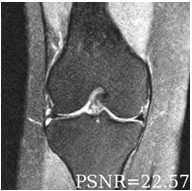

Deep learning based techniques achieve state-of-the-art results in a wide range of image reconstruction tasks like compressed sensing. These methods almost always have hyperparameters, such as the weight coefficients that balance the different terms in the optimized loss function. The typical approach is to train the model for a hyperparameter setting determined with some empirical or theoretical justification. Thus, at inference time, the model can only compute reconstructions corresponding to the pre-determined hyperparameter values. In this work, we present a hypernetwork based approach, called HyperRecon, to train reconstruction models that are agnostic to hyperparameter settings. At inference time, HyperRecon can efficiently produce diverse reconstructions, which would each correspond to different hyperparameter values. In this framework, the user is empowered to select the most useful output(s) based on their own judgement. We demonstrate our method in compressed sensing, super-resolution and denoising tasks, using two large-scale and publicly-available MRI datasets. Our code is available at https://github.com/alanqrwang/hyperrecon.